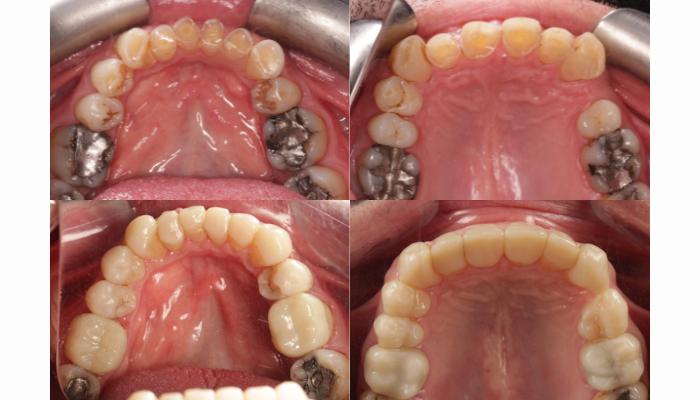

Dalla foto in alta a sinistra a quella in basso a destra, la stampa 3Dè stata in grado di mitigare la grave usura dentale del paziente.

Il Dr. Gakhal ha adottato un approccio incentrato sul paziente, discutendo gli obiettivi del trattamento. Il processo includeva la protezione della struttura dentale rimanente, il ripristino della dimensione verticale occlusale (la distanza naturale tra le mascelle superiori e inferiori quando la bocca è chiusa) e il miglioramento dell’estetica dentale mantenendo il trattamento il meno invasivo possibile. Il caso del paziente presentava diverse sfide. Tra queste, corone cliniche fortemente accorciate (le parti visibili dei denti sopra la gengiva) con rischio di quasi esposizione della polpa. C’era anche una compensazione alveolare, uno spostamento dell’osso mascellare che si verifica con l’usura dei denti e può influenzare l’occlusione. Altri problemi includevano zenit gengivali asimmetrici, cioè un’altezza delle gengive irregolare che incide sulla linea del sorriso, e canini posizionati verso l’esterno, rivolti verso le guance. Ognuno di queste problematiche richiedeva un’attenta pianificazione per ottenere un risultato naturale e funzionale.